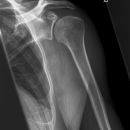

Schulter seitlich (Y-View)

Bei Luxation zusätzlich zur glenoidtangentialen Aufnahme problemlos durchführbar! Axiale Aufnahme schmerzbedingt meist nicht möglich.

Beurteilungskriterien

- Skapula bildet sich als Y ab

- Humeruskopf projiziert sich in das Glenoid? Luxation? Luxationsrichtung?

- Weite des subacromialen Raumes exakt nur in der 10 – 15° nach kaudal angulierten Aufnahme bestimmbar („Morrison, Outlet View“)! Normalerweise 1 - 1,5 cm, < 6 mm -> wohl pathologisch, Impingment wahrscheinlich

- Normvarianten: Os glenoidale (akzessorischer Ossikel kaudal des Glenoids), persistierende Akromion- oder Korakoidapophyse, entwicklungsbedingte Pfannenranddefekte

- Schulterluxationen:

- Anteriore Luxation (2) 95%= anteriore infraglenoidale Luxation, Kopf liegt vor Glenoid

- Posteriore Luxation (2) 3%: wird häufig übersehen! Kopf liegt hinter Glenoid, Hochstand des Humeruskopfes, fixierte Innenrotation des Humeruskopfes => atypische Projektion des Humeruskopfes: “ drumstick or bulb appearance“ (Birnenform), Muldenzeichen („trough line“), „rim sign“ in der ap bzw. glenoidtagentialen Aufnahme.

Zweite Ebene, z.B. transskapuläre Aufnahme zeigt die Richtung der Luxation. Cave. rein klinische Diagnose!

- Begleitverletzungen? (-> heute umfassend mit CT/MRT zu beurteilen)

- Tuberculum majus (15%)

- Pfannenrand

- Hill- Sachs Läsion = Dorsokraniale Humeruskopf-Impressionsfraktur (50%) (Aufnahme der 1. Wahl: Stryker oder CT)

- umgekehrte Hill-Sachs Läsion = anteromediale Impression nach hinterer Luxation

- Bankart-Läsion: Abriss des vorderen Labrum-Kapsel-Komplexes bzw. Abrissfraktur des vorderen unteren Glenoidrandes (-> CT-Athrographie, Arthro-MRT)